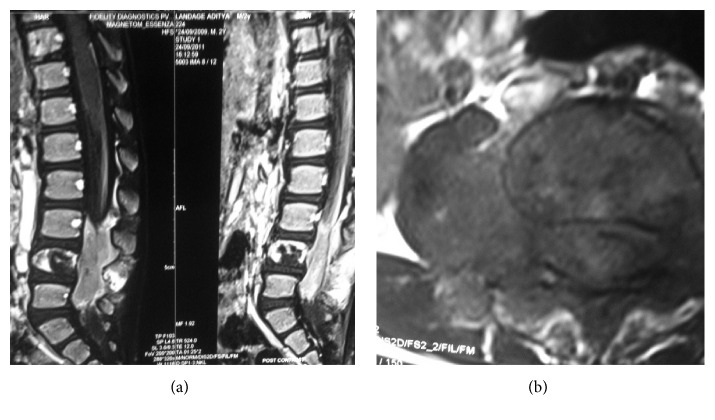

MRI of the lumbosacral spine (Figures 1(a) and 1(b)) revealed a soft tissue mass arising from the pedicle of L4 vertebral body invading the spinal canal, posterior elements, and Right Psoas muscle with destruction of the L4 vertebral body.

Figure 1.

Sagittal projection of postcontrast T1 and T2 images demonstrating destruction of L4 vertebral body and tumour mass invading the spinal canal and posterior elements at L3, L4, and L5 vertebral levels. Axial projection of postcontrast T2 MRI image demonstrating tumour mass arising from the pedicle of L4 vertebra invading the spinal canal and the Right Psoas muscle.